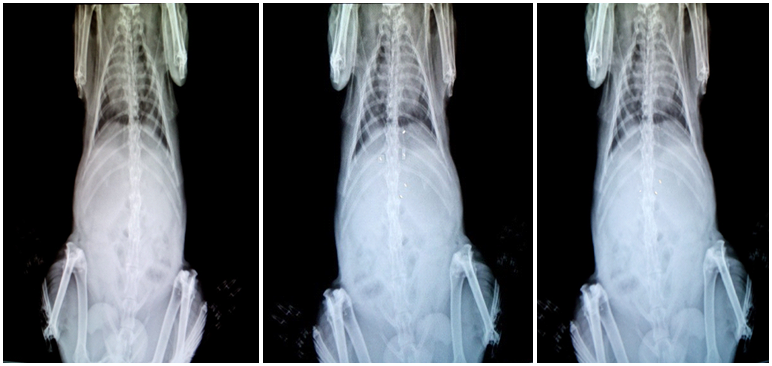

In vivo floating behaviour study

Healthy rabbits weighing approximately 2 kg were used to assess in vivo floating behaviour. Ethical clearance for the handling of experimental animals was obtained from the institutional animal ethical committee (Registration No. 1321/PO/ReBi/S/10/CPCSEA) constituted for the purpose. The animals were housed in individual cages, and the experiments were carried out in a sanitized room. Rabbits fasted for 12 h and the first X-ray photograph was taken to ensure the absence of radio-opaque material in the stomach. Barium sulphate was incorporated into the microballoons to make the microballoons X-ray opaque. The amount of barium sulphate was kept 10 mg per g of microballons to ensure visibility by X-ray and to enable the microballoons to float. Rabbits were made to swallow barium sulphate loaded microballoons with sufficient quantity of water. During the experiment, rabbits were not allowed to eat but the water was provided ad libitum. At predetermined time intervals (0, 6 and 12 h) the radiographs of the abdomen were taken using an X-ray machine [24-25].

In vivo floating behavior study

The in vivo floating behavior of microballoons loaded with barium sulphate was investigated by radiographic images (X-ray photographs) of rabbit’s stomach at periodic time intervals. The radiographs obtained at 0, 6 and 12 h are shown in fig. which indicates a uniform distribution of formulation over the gastric fluid and in vivo duration of floating for more than 12 h.

(a) (b) (c)

Fig. 7: X-ray photograph of rabbit stomach: (a) without drug loaded microballoons (b) showing buoyancy of microballoons after 6 h (c) showing buoyancy of microballoons after 12 h